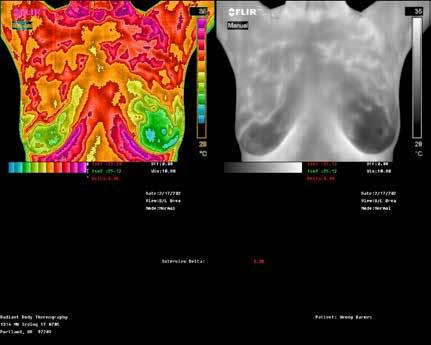

Breast Screening

RADIANT BODY THERMOGRAPHY

Candace Parmer

Clinical Thermographic Technician

503-775-1812

RadiantBodyThermography.com